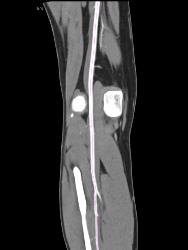

Patent Popliteal Artery and Trifurcation